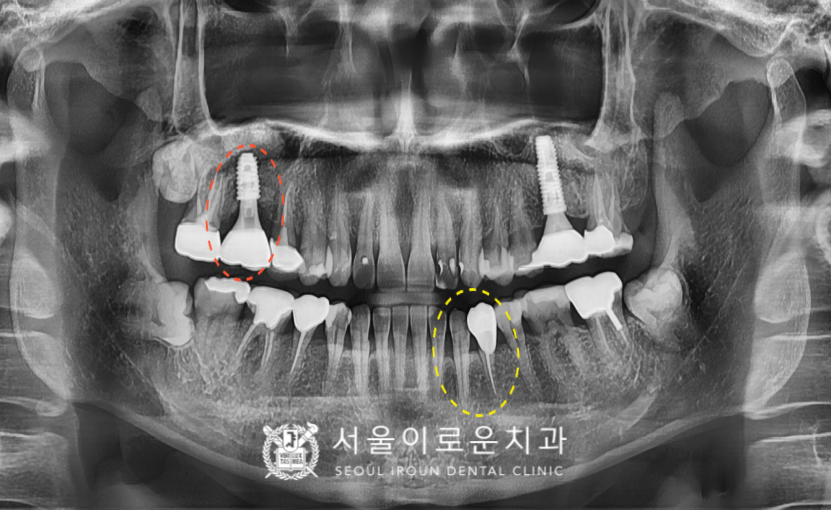

술 후 파노라마와 3D-CT를 통해

상악동 거상술을 동반한 임플란트가

안정적으로 식립된 것을

체크하였답니다.

임플란트와 잇몸뼈가

단단히 결합될 때까지 충분히 기다린 뒤

보철과정까지 성공적으로

마무리 해드렸답니다.

서울이로운치과에서

모든 치료가 마무리 된 후

촬영한 파노라마 사진입니다.

임플란트 / 레진치료 /

신경치료 / 크라운치료를

모두 깔끔하게 잘 도와드렸답니다.